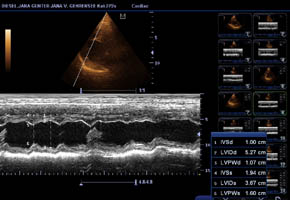

Gesundheitsstatus vom 26.11.2018 Die Röntgenbilder zeigen keinen Hinweis auf HD oder ED bei Lena vom Gehrensee. Die veterinärmedizinischen Untersuchungen von Jana auf HD, ED u. DCM und die Zuchtzulassungsprüfung wurden erfolgreich bestanden.

Die Gelenke sind HD und ED - frei, das Herz ohne Befund. Vor dem Hintergrund, dass seit 5 Generationen alle Zuchthündinnen bis ins hohe

Alter eine hervorragende Herzleistung hatten und bei ihnen niemals Herzprobleme auftraten, sind solche aufwendigen Ultraschalluntersuchungen

eine reine Routinesache. Hinzu kommt, dass die Mutterhündin (im Ruhestand) "Indra" mit 6 Jahren durch eine extrem hohe Fitness in Bezug

Herzultraschall von Lena vom Gehrensee zur Vermeidung von DCM

Durch Klick auf die Übersicht können die Herzdaten eingesehen werden.

Der Herzcheck ergab keinen Hinweis auf DCM.